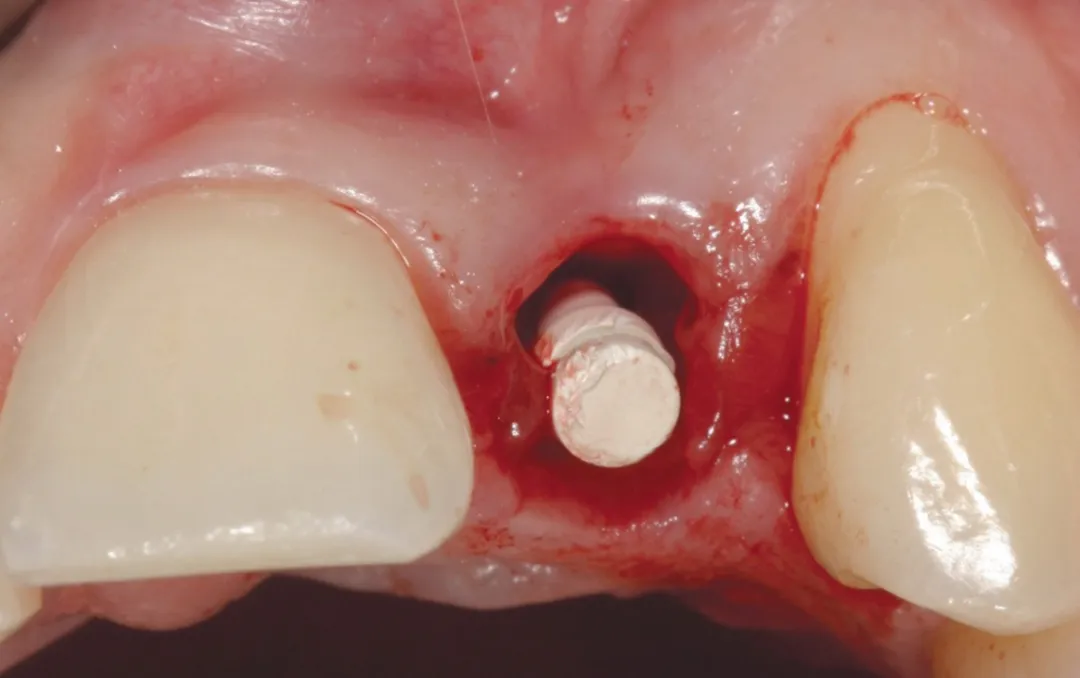

图 24 :植入 Axiom® 2.8 x 14 种植体。

图 25 :种植体就位。

图 38 :拔牙后种植位点。

图 39 :种植体就位。